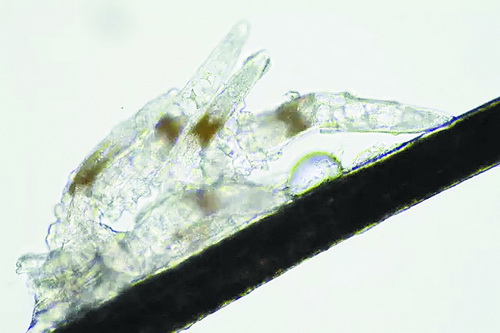

顯微鏡下長在睫毛中的螨蟲

冬天來了,氣溫降低,睫毛上的“隱形殺手”蠕形螨卻沒有要冬眠的意思。廈門大學(xué)附屬廈門眼科中心11月初開設(shè)蠕蟲性瞼緣炎門診以來,每天來查螨的市民都特別多,短短一個多月,已有近千人在顯微鏡下見到長期寄居在自己睫毛上,朝夕相處,卻素未謀面的蠕形螨。